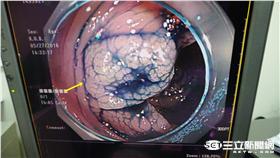

嚇!男子長期胃食道逆流 驚罹食道癌

別輕忽俗稱「火燒心」的胃食道逆流!就有一名老翁因胃食...

大便習慣突然改變?恐是直腸癌前兆!

大便習慣突然改變?便血、大便稀爛不成形?千萬別輕忽!...